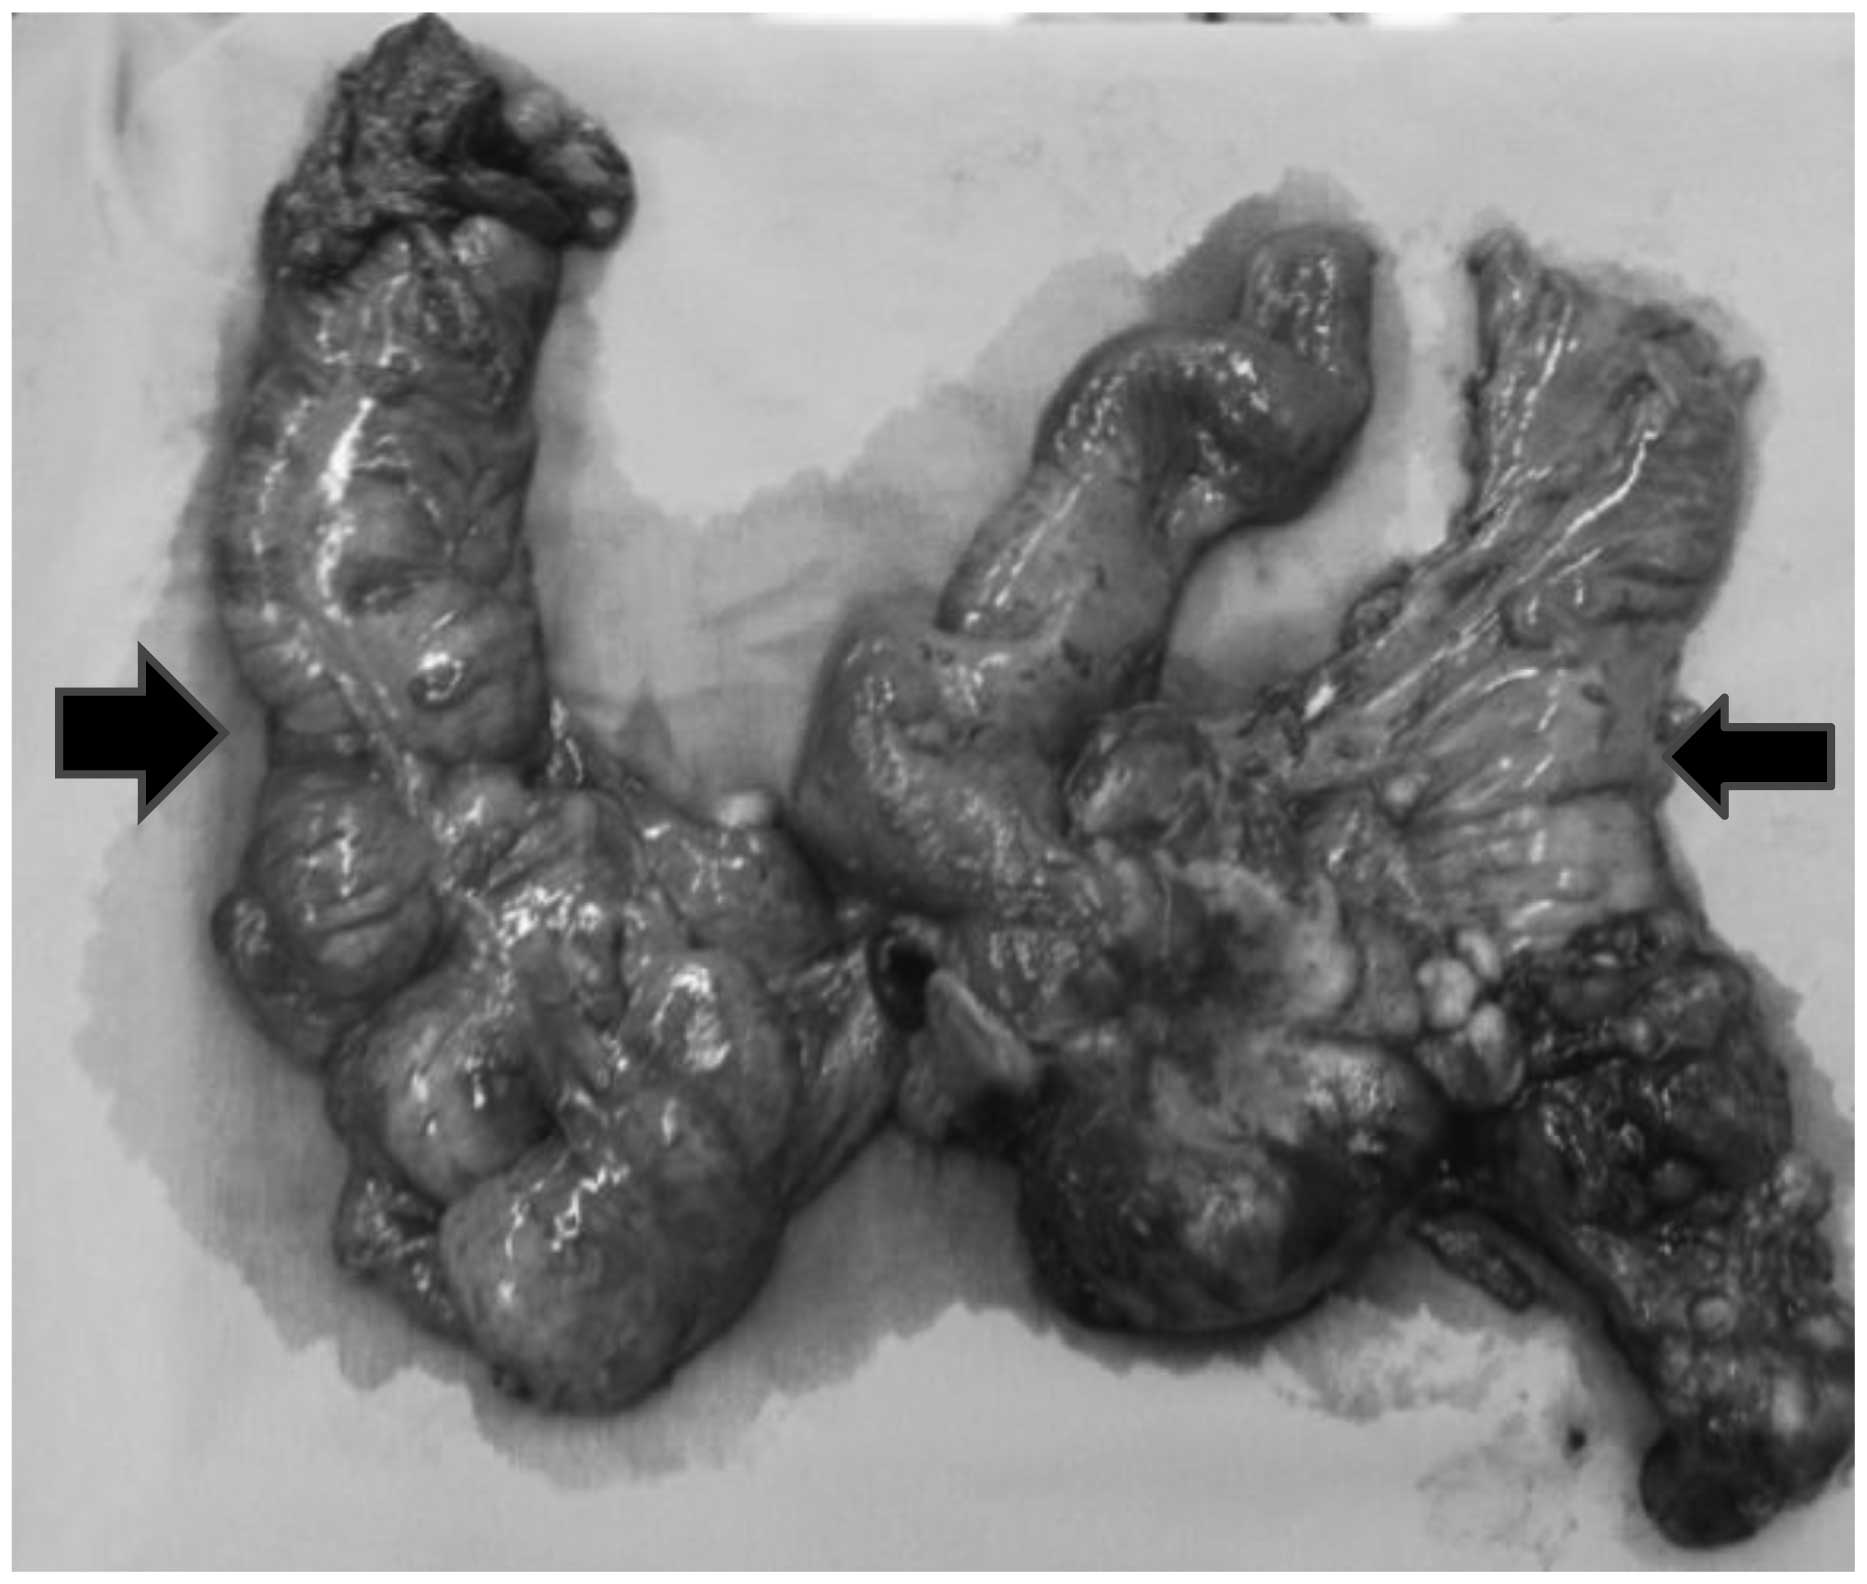

During a laparotomy, right hydronephrosis was observed that was caused by a large tumor involving the cecum, terminal ileum and right ureter. Implantation of the tumor was identified in the right colon, liver and pelvic cavity, with involvement of the rectum. Consequently, a resection of the terminal ileum, cecum, right colon, distal segment of ureter, sigmoid colon and middle rectum was performed. In addition, a right, left and pelvic peritoniectomy was performed. Intestinal reconstruction was re-established with an ileo-transverse anastomosis associated with a left colostomy, implantation of a proximal urether into the bladder and insertion of a double-J catheter (Figs. 3 and 4). The post-operative follow-up was uneventful, however, deep vein thrombosis occurred in the right lower limb 20 days after surgery.